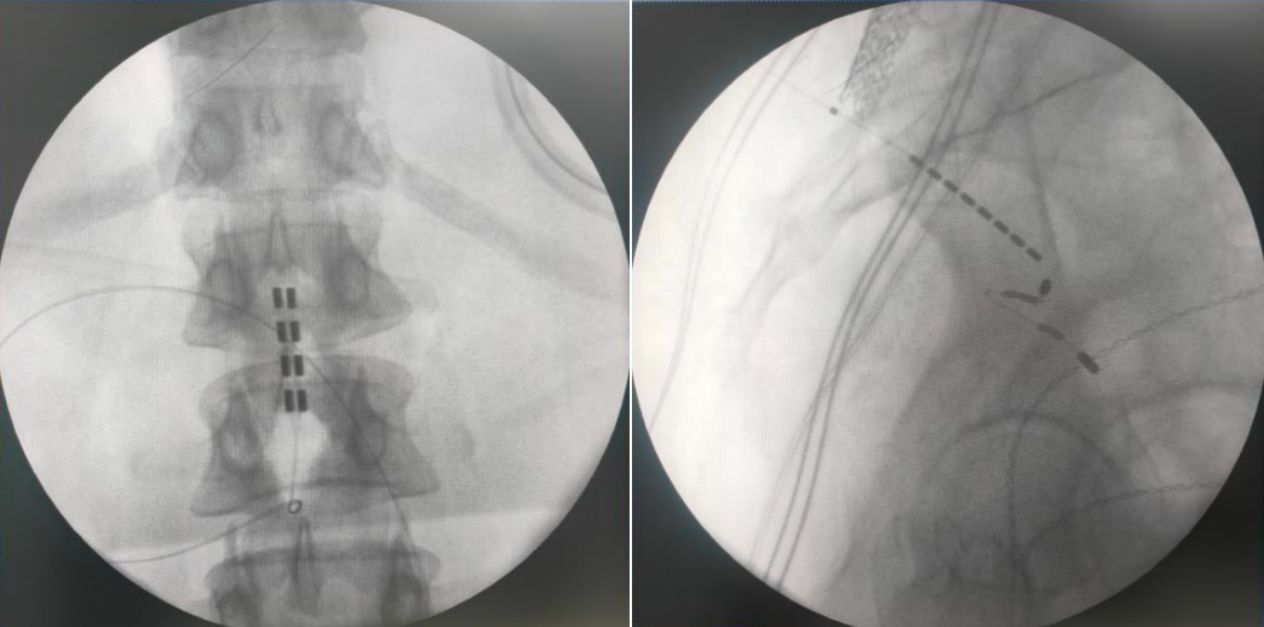

由于該患者為脊髓拴系,脊髓位置偏低,而且脊柱裂合并骶椎骨性解剖畸形給骶孔穿刺帶來了非常大的難度,但是通過術前的系統評估以及術中電生理監測,李萃萃主任團隊將一根穿刺電極精準置入S3骶孔位置以改善二便功能,另一根4-4排布的片狀電極覆蓋L1-2節段(患者脊髓低位,放置位置需根據患者情況個性化調整)以調控下肢肌張力異常和感覺障礙。術中測試顯示,骶神經刺激可有效引發二便感知,脊髓電刺激則完整覆蓋臀部及雙下肢。